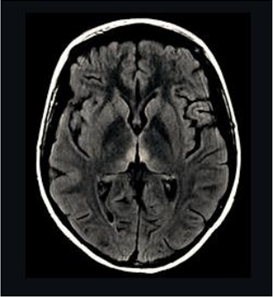

Mulher de 22 anos chega ao pronto atendimento com história de dificuldade para caminhar por falta de equilíbrio há três meses. Evoluiu com piora gradual e hoje deambula somente com apoio. O marido relatou que a paciente realizava atividade física por várias horas diariamente, abandonando a prática devido ao quadro clínico, e que fazia dieta constantemente. Ao exame clínico: paciente muito emagrecida, IMC 16, taquicárdica, sonolenta, com ataxia de marcha, desorientada no tempo e no espaço e com alteração na motilidade ocular extrínseca. A paciente foi internada para investigação. Dois dias após, apresentou piora e foi transferida para a UTI, em coma. A imagem da ressonância magnética de crânio evidenciou a alteração exemplificada pela imagem ao lado e o exame de liquor foi normal. Em relação ao caso apresentado, é correto afirmar:

Provas